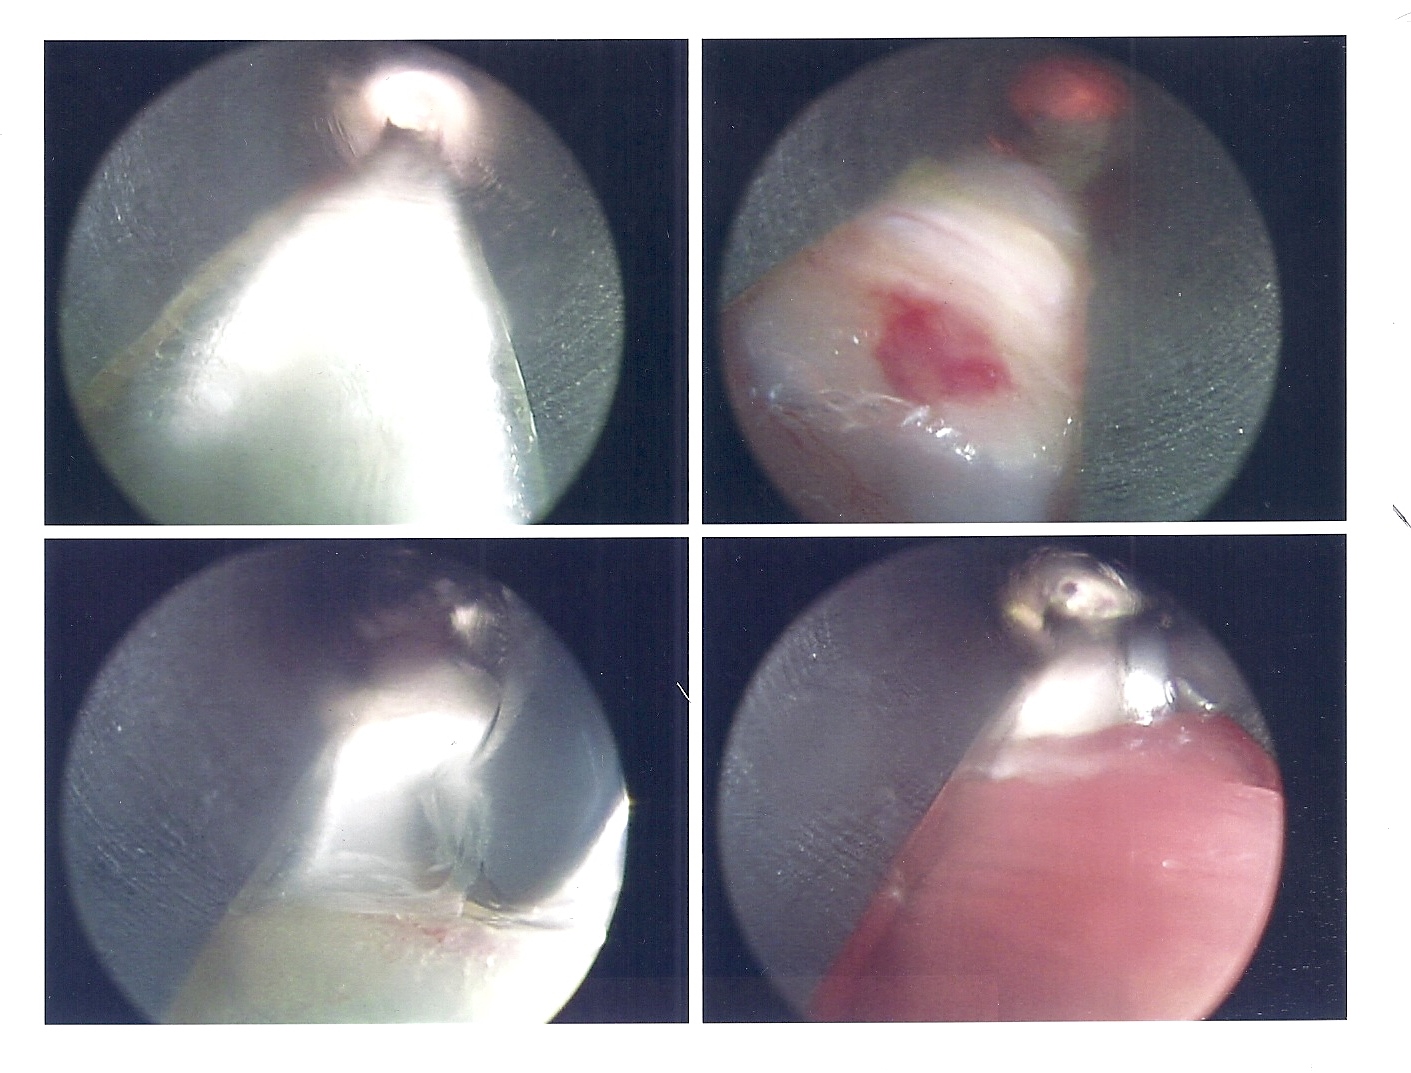

Here are the Endoscopic Camera Surgical Photos, (click on photos to enlarge)

Here is my YouTube video of Dr. Gent visiting me after I was well awake in the recovery room. The surgery was about 40 minutes and Dr. Gent said there was a good release of the muscle and complete full-range ankle dorsiflexion after the slice through the Gastroc and Soleus Aponeurosis. Surgery started before 9am and I was back to my hotel around noontime. The surgery was done under General Anesthesia. My lower leg is very comfortable in its plaster splinting and ace wraps and my TENS unit leads are applied underneath for help in pain control.